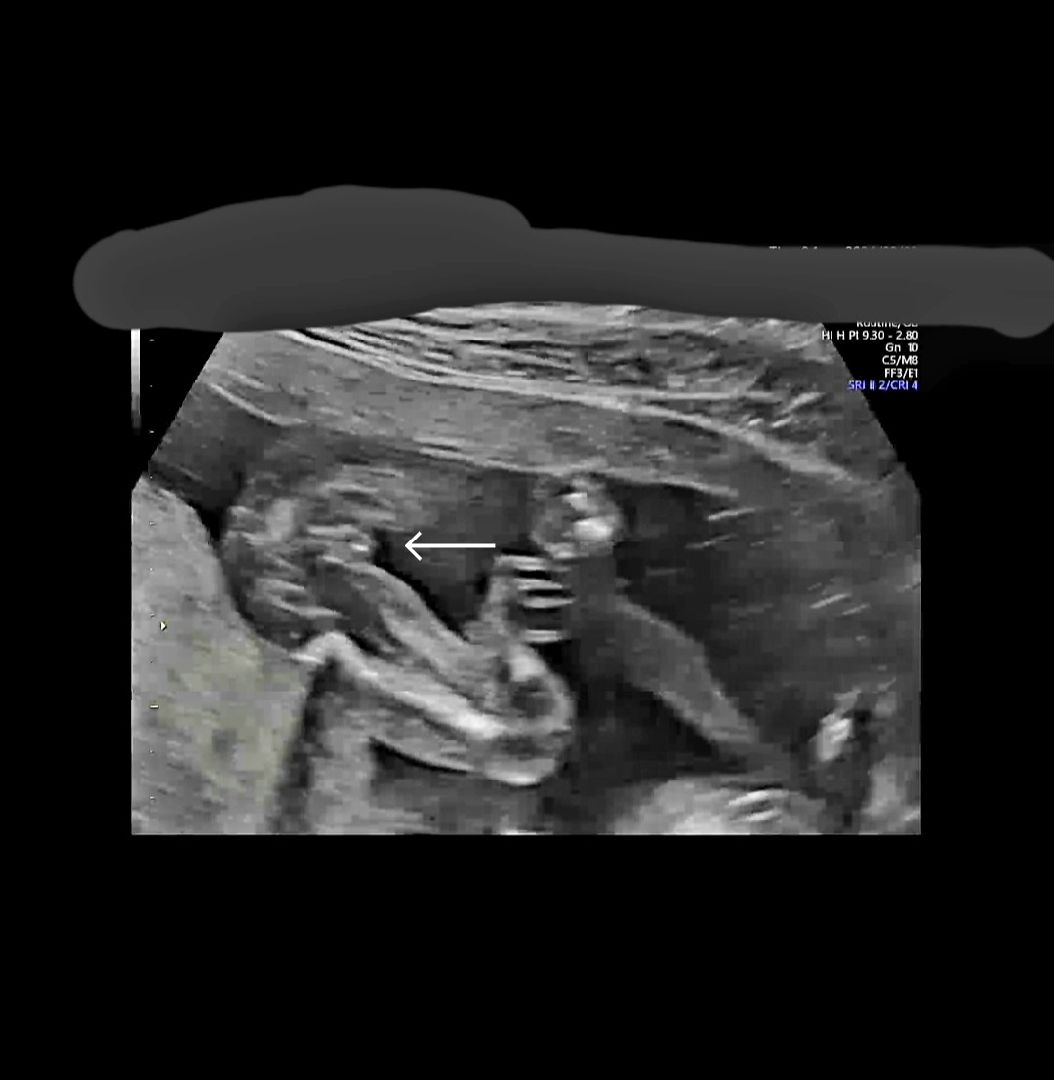

아들vs딸....과여언...

아들같기도 딸같기도...너무어려운 초음파

대음순 100퍼딸 ㅎ

살짝 미사일 같아 보이기도 하는뎁ㅋ 저는 월욜에가서 미사일보고 왔어용ㅋ

딸같아용 ㅋㅋㅋㅋㅋㅋㅋ 저희 아들은 아주 확실하게 뽝!!! 아들은 딱!!!!보여용!!!

저희아들인데 미사일이 걍 보이거든요ㅋㅋㅋㅋ

그렇군요!??제눈엔 가운데가 아주 잘보여서ㅋㅋ저게미사일아닌가싶지만 아들은 더 확실한 미사일이 있나봅니다!